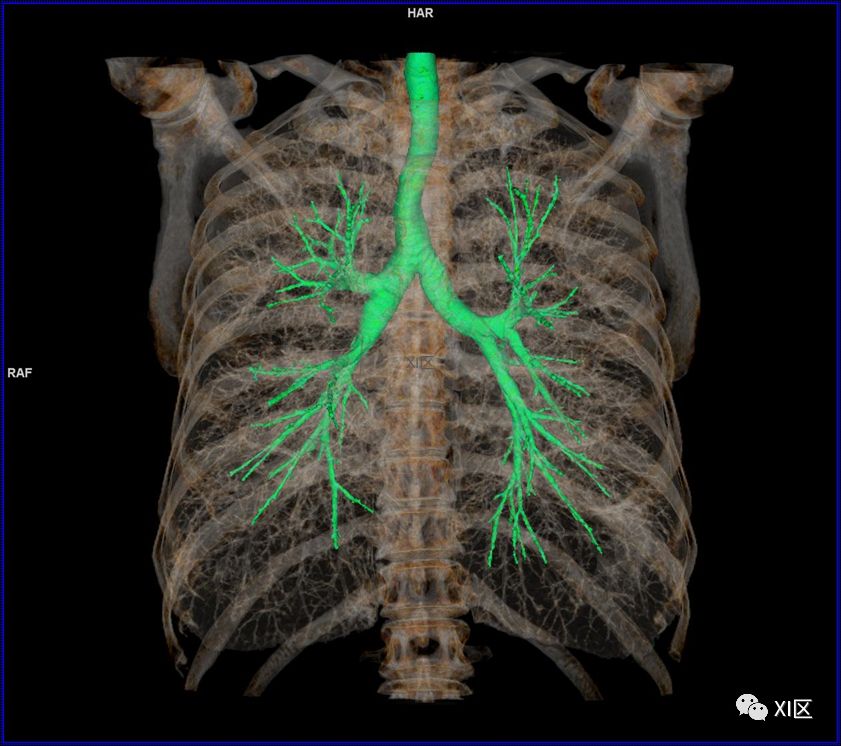

前后位,双侧位,后前位显示气道肺与胸部骨骼的关系

气管树与胸部其他结构的关系